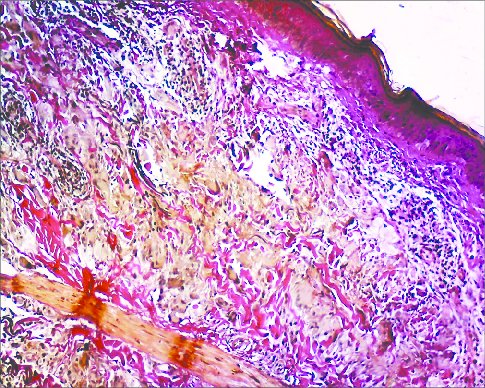

📌 Masson Fontana

يستهدف جزيئات الميلانين

وتظهر كالاتي

Melanin اسود

Nuclei احمر